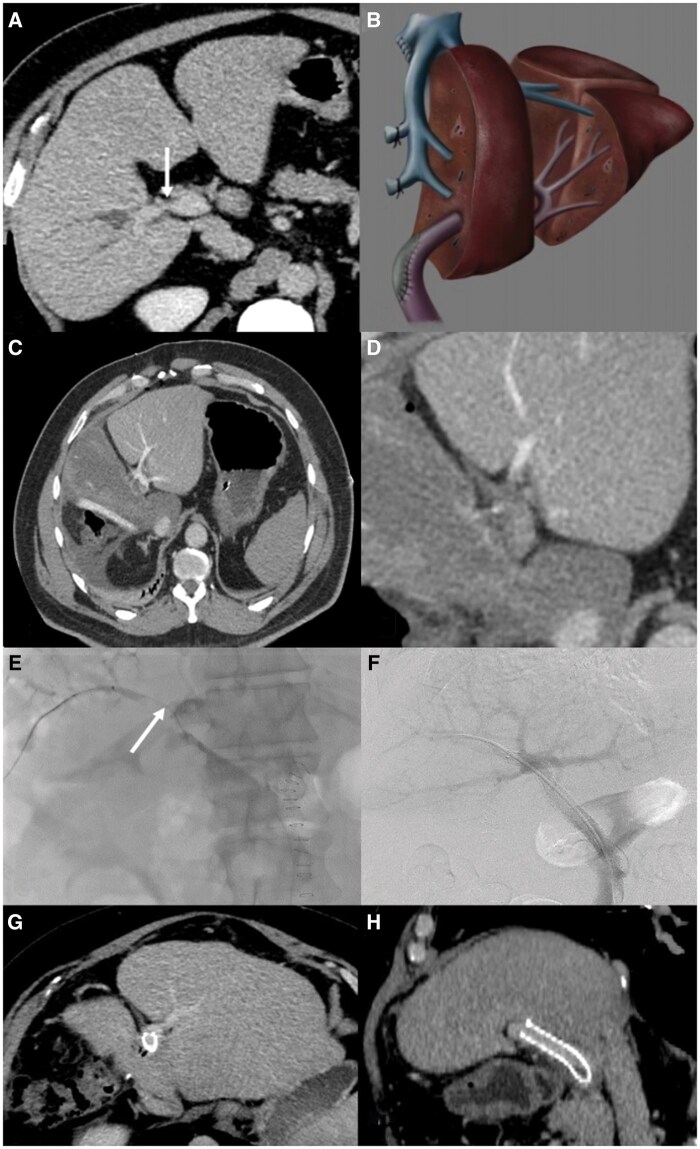

Currently, portal vein (PV) resection is performed in 10%-40% of liver resections performed for hilar cholangiocarcinoma (HC). The defect is generally repaired with a patch of an autologous vein graft or end-to-end anastomosis after complete separation of the main PV trunk and the left PV. Postoperative PV thrombosis is a severe complication occurring in 2%-9% of patients requiring PV reconstruction. Here in, we presented a 55-year-old man with abdominal pain without hyperbilirubinaemia who was diagnosed with HC. The patient underwent right hepatectomy, extrahepatic biliary resection, and PV resection. The PV defect was repaired with autologous umbilical vein graft. Following the operation, acute PV thrombosis was encountered postoperative day 1. We conducted the treatment of the early acute PV thrombosis by intraportal tPA and PV stenting with endovascular approach.